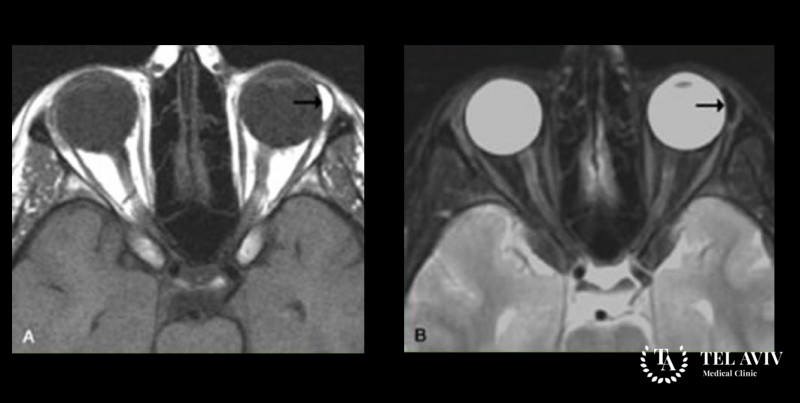

Котомковидная дермоидная киста орбиты – это доброкачественная опухоль которая развивается при нарушениях бласто- и эмбриогенеза. Новообразование имеет овальную или округлую форму, а его стенки состоят из соединительной ткани. Для данной патологии характерно медленное течение и постепенное смещение глазного яблока вперед (экзофтальм). Из-за этого ограничиваются функции экстраокулярных мышц, появляется диплопия. Диагностируется заболевание, как правило, у людей старше 15 лет.

После офтальмологического исследования и сбора анамнеза врач может назначить следующие диагностические исследования: рентгенография и компьютерная томография. В большинстве случаев с постановкой диагноза не возникает проблем. Однако очень важным является этап проведения дифференциальной диагностики. Необходимо исключить сосудистую опухоль, невриному, опухоль слизистой железы, холестеатому и остеомиелитому.